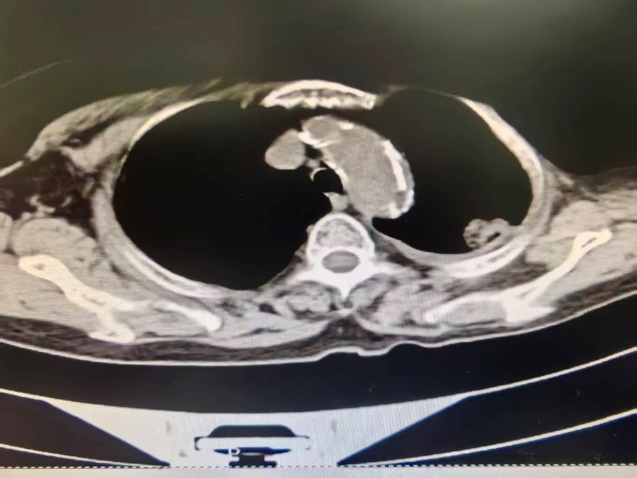

临床资料: 女,73岁,14天前体检发现左肺占位性病变合并胸腔积液,无发热、咳嗽、咳痰、胸闷等。既往史:高血压1年;20余年前当地医院“左乳腺癌切除术”,具体不详。影像学:左乳术后,左乳缺如;左肺上叶及右肺中下叶可见片状及云絮状高密度影,边界不清,左肺上叶胸膜下可见实性结节影,大小约28mm×18mm,可见分叶。双肺上叶可见磨玻璃密度结节影,较大者直径约10mm,左肺上叶心影旁另可见一实性小结节影。左侧胸腔可见积气积液影。